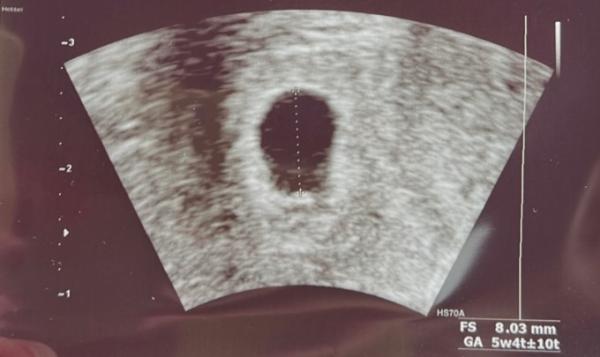

Leider ist die FH beim US bisher zweimal leer gewesen, allerdings gut gewachsen. Laut FÄ spricht nichts konkretes gegen eine intakte SS, ich sollte mir aber auch klar sein, dass es ein Frühabort/Windei sein könnte. Mein Bild hab ich diesmal trotzdem mitbekommen…

Die FH ist ca 8mm groß und ich wurde auf 5+4 datiert, obwohl meine Periode wie gesagt eigentlich ca 9ssw vorgibt.